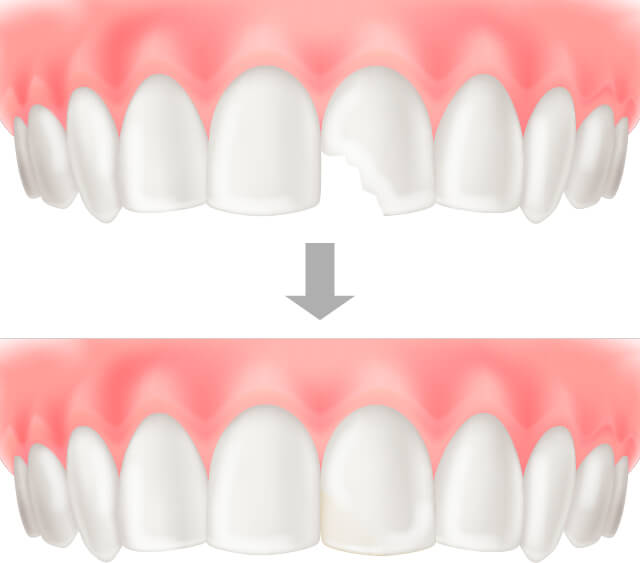

レジン前装冠(前歯被せ物)

前歯に対しての被せ物治療。コンポジットレジンでは対応できない大きなむし歯や根管治療終了後のケースに使用される。

裏面は金属で強度を保ち、表面は白いレジンで覆われているが、レジンに汚れや着色が付着しやすくむし歯の再発や審美的に優れなくなる可能性がある。

セラミッククラウン(前歯、奥歯被せ物)

ダイレクトセラミック、セラミックインレーで対応できないほど大きなむし歯や根管治療終了後に行う被せ物治療。

セラミックのため審美性に優れ、汚れや着色が付着しづらい。金属は、経年変形するがセラミックは変形しないためむし歯の再発率を格段に軽減することができる。

技工士が作成するため、型取りと作成日数が必要。